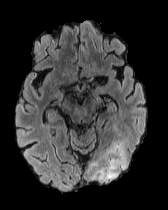

When computing with Eq. (9), the sum of the two components may not produce a perfectly coherent result. However, the incoherence is resolved by the next diffusion step, which fuses the two components better. This would not be the case if we simply computed with DDPM and then applied the mask only at the end of the sampling process. An illustration of this effect is presented in Figure 3, where we can observe how the normal image, generated by applying the mask solely at the conclusion of the sampling process (b), exhibits some artifacts and lacks a seamless transition between the edited and unedited regions.

In Figures 2 and 4 we display examples of healthy images and anomaly maps obtained with the different approaches. We can observe that f-Ano GAN is not able to generate credible counterfactuals and generally produces images of poor quality and unrealistic appearance. On the other hand, the approaches based on diffusion models are able to create more high-quality results. However, the ones obtained with CG and CFG seem to present some artifacts, which may not only impact the realism of the counterfactual examples but also the precision of the anomaly maps obtained from them. In order to better quantify the capability of these methods to accurately segment pathological areas, we compute the Dice scores of the anomaly maps they generate.

In Figure 5 we plot the dice scores obtained for different values of these hyperparameters. As we can observe, we obtain the best performance when employing 500 noising steps and selecting the pixels in the percentile of the saliency maps. In Figure 7 we display counterfactuals obtained with different noise levels. We can observe how smaller values of the noise parameter don’t allow the diffusion model to modify the image to an adequate degree, while bigger values introduce artifacts that impact the image quality of the generated image, consequently also hurting the dice score of the corresponding anomaly map.